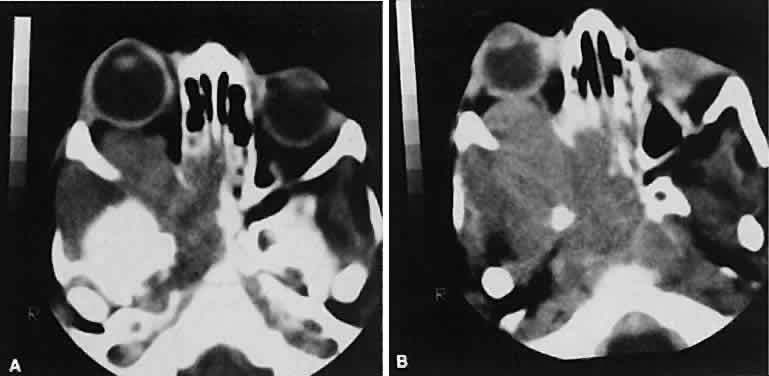

The muscle belly has a smooth contour with no edema of the adjacent orbital fat. We recently evaluated a patient with a referral diagnosis of Graves' orbitopathy. The patient was euthyroid but had severe orbital congestion typical of advanced Graves' orbitopathy. Imaging showed “dirty” orbital fat and lateral rectus muscle morphology that seemed atypical (Fig. 8). Biopsy specimen results showed a low-grade lymphoma. Hypertrophy of the medial rectus muscle can cause the medial wall to bow in toward the ethmoidal sinus from the chronic effects of pressure on the bone. The hypertrophied muscles also can give rise to a compressive optic neuropathy in the orbital apex as the enlarged muscles take their origin from the anulus of Zinn. Axial views of the apex show an apparent mass if the inferior rectus muscle is enlarged. It is imperative that additional views, sagittal or preferably coronal, be obtained to show the true nature of this apparent mass. Intracranial fat prolapse, seen by CT, may be another sign of optic neuropathy.44 An optic neuropathy also can be seen with relatively normal-sized EOM. An expanded fat compartment with optic nerve stretch has been associated with an optic neuropathy.45,46

Fig. 8. Low-grade lymphoma confined to orbit mistaken for Graves' ophthalmopathy in a 65-year-old man. A. On the axial view, orbital fat appears “dirty” with marked increase in soft tissue stranding. Muscles do not have a smooth appearance, lateral rectus muscles have lumpy appearance (arrow), and both lateral rectus muscles are disproportionately large for what typically is seen in Graves' orbitopathy. B. Coronal view also shows dirty orbital fat. Note left inferior rectus, which is small (arrowhead), and also is atypical in Graves' orbitopathy when there is enlargement of the other extraocular muscles.